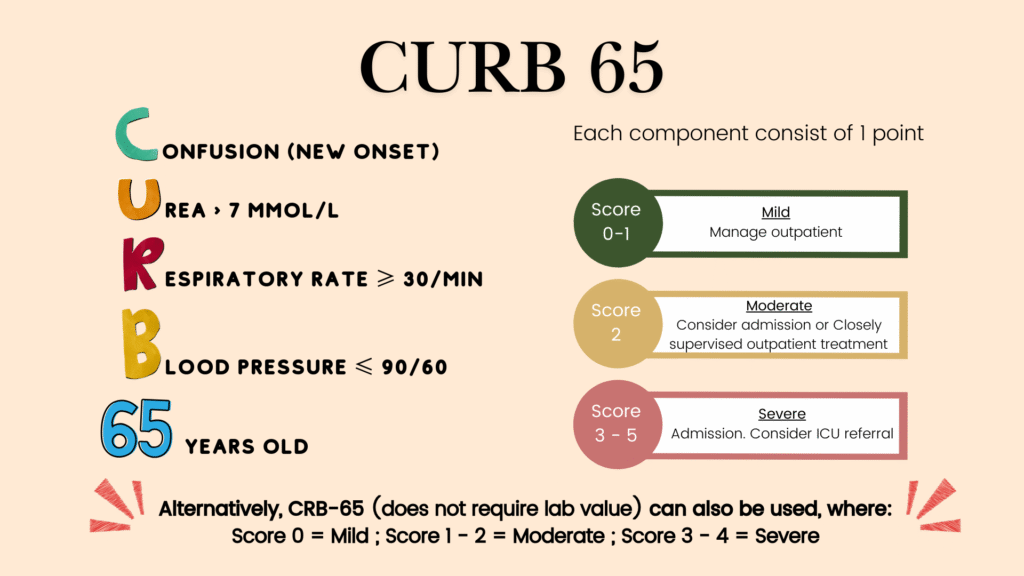

Prognostic scoring tools

In addition to the factors mentioned above, there are few prognostic scoring tools that may be used to support our decision on site of treatment.

These include:

- Pneumonia severity index (PSI) – useful for identifying low-risk patient that can be safely treated as outpatient.

- CURB-65/CRB-65

- SMART-COP

The American Thoracic Society (ATS) guideline recommends PSI over CURB-65 as PSI is able to identify larger proportions of low-risk patients that can be treated as outpatient. In regards to CURB-65, there is paucity of evidence regarding its effectiveness/safety as decision aid in guiding initial site of treatment. Nevertheless, NICE guideline do recommend using CURB-65/CRB-65 for pneumonia severity assessment.

In our Malaysia NAG guidelines, CURB-65/CRB-65 and SMART COP are recommended scoring tools to aid in decision making on initial site of treatment.

However, in the ATS guideline, SMART COP is only used when patient has already been admitted to the hospital and it is used to identify patients who need vasopressor &/or mechanical ventilation and thus ICU admission.

Among these scoring tools, CRB-65 might be more suitable for primary care setting as it does not require any lab results/imaging.

It is important to keep in mind that these are used to support but not replace clinical decision making.

PSI and SMART COP are not listed in detail here as they require lab tests that may not be available in primary care setting.